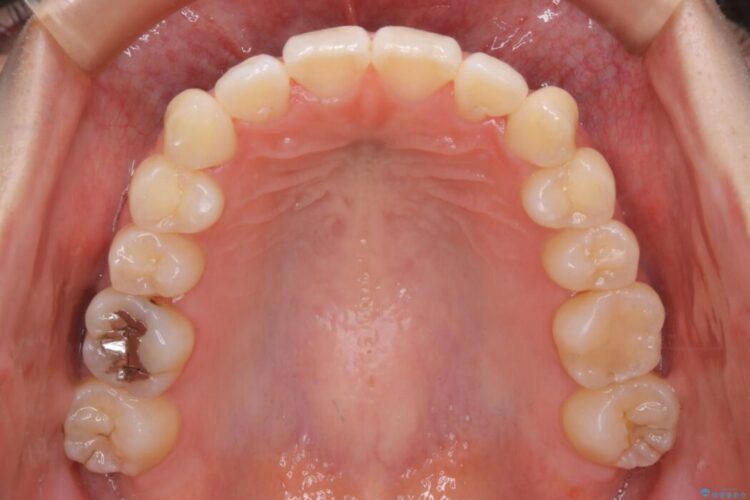

治療後について

治療前と治療後を見比べると口元の見た目の変化が良く分かります。

本症例では奥歯から順に移動させるため前歯の変化を感じるには時間が掛かりましたが、インビザライン装置とマイクロインプラントを併用することで健康な歯を抜歯することなく歯列をきれいに整えることができました。